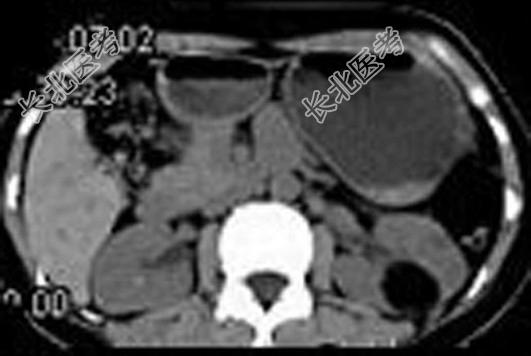

- 多项选择题女,38岁, 体检时B超在左肾探及一中强回声光团,边界清, 内部回声均匀,CT检查如图所示, 下列说法正确的是 ( )

A、左肾中部靠后方可见一类圆形低密度病灶

B、病灶与周围肾组织界限清楚

C、病灶密度为脂肪密度

D、考虑为左肾血管平滑肌脂肪瘤